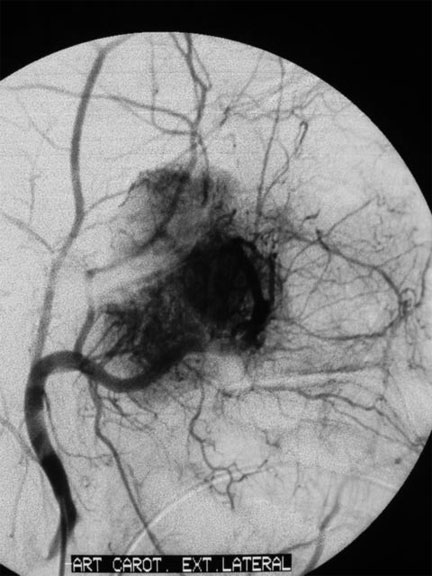

CASO 1 : Embolización del angiofibroma nasofaringeo juvenil Antes del tratamiento de embolización Despué del tratamiento de embolización